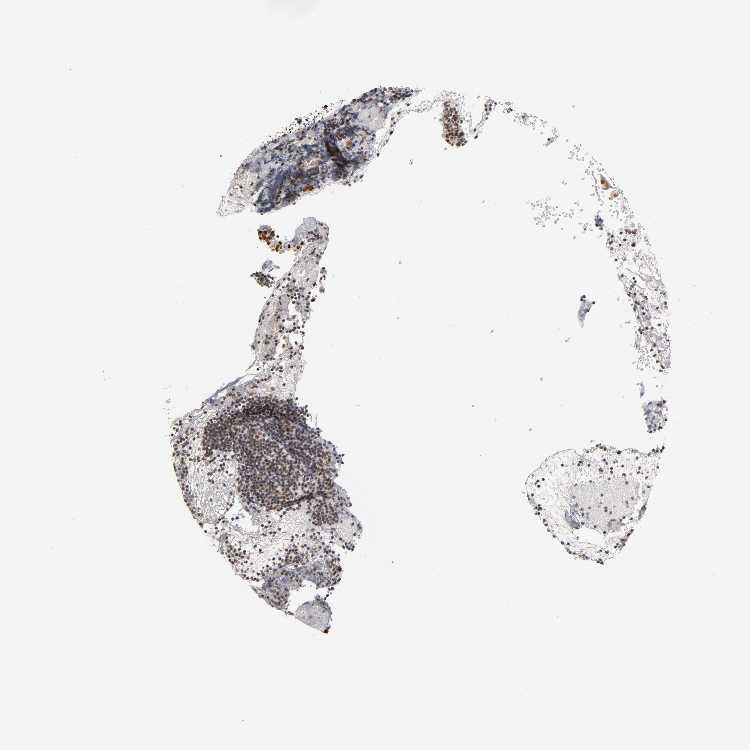

TONSIL - Antibody stainingi

Antibody staining in the annotated cell types in the current human tissue is reported as not detected, low, medium, or high, based on conventional immunohistochemistry profiling in selected tissues. This score is based on the combination of the staining intensity and fraction of stained cells.

Each image is clickable and will lead to virtual microscopy that enables deeper exploration of all samples and also displays staining intensity scores, fraction scores and subcellular localization as well as patient and tissue information for each sample.

Antibody HPA004345

Germinal center cells Medium

Non-germinal center cells Medium

Squamous epithelial cells High